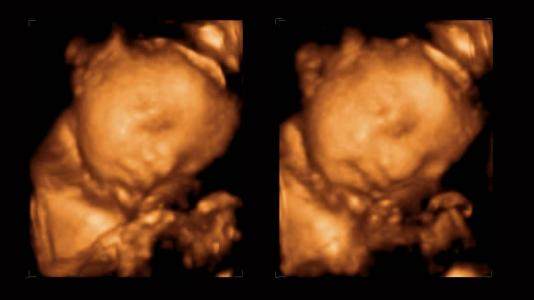

脐带绕颈就是脐带缠绕在宝宝脖子上,这是一种很常见的现象。大多数是绕颈一圈,少数绕颈两圈,三圈以上的很少见,主要的原因有脐带过长,羊水过多,胎儿体形较小,这样胎儿活动范围就大,在子宫里翻转,就会容易导致绕颈!多数情况下,脐带绕颈会自动解锁!

其实,脐带绕颈1-2周并不可怕,可怕的是宝宝若太调皮,在妈妈肚子里不停地转啊转,绕上个两三周的!为什么会发生脐带绕颈?脐带绕颈就不能顺产?胎儿脐带绕颈三周,危害到底有多大?